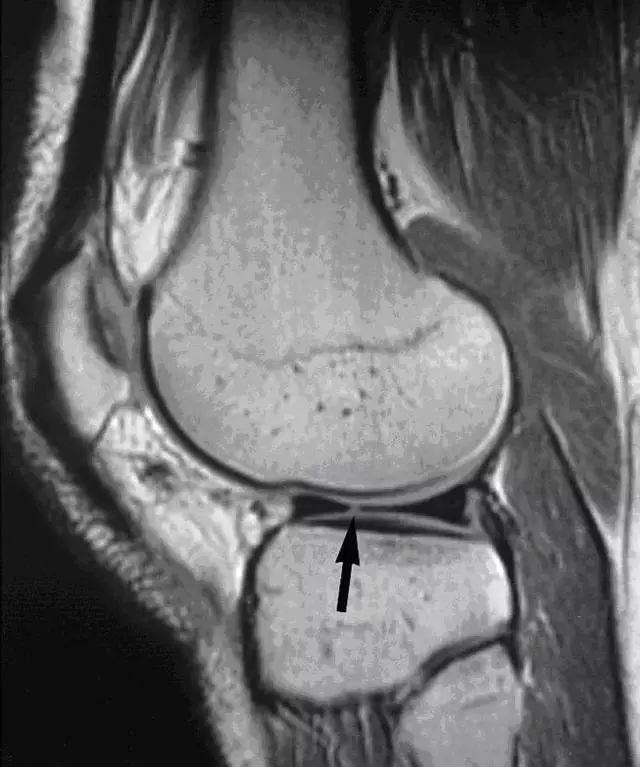

正常半月板 MRI

正常半月板在 MRI 上显示的是低信号,呈「领结形」。外侧半月板呈 C 形,且横断面前后较一致;而内侧半月板较大,曲率较低,后角相较于前角较宽和厚。

内侧半月板外缘完全附着在关节囊上,外侧半月板前角和体部附着在关节囊上,而后角大部分附着在关节囊上,中间由腘肌半月板上下纤维束连接半月板和关节囊,上下纤维束中间形成一裂孔,裂孔中有腘肌腱穿过。示意图如下图 1 所示,正常内外侧半月板 MRI 如图 2 所示。

图 1 可看到外侧半月板后角由腘肌半月板纤维束形成裂孔,其中通过腘肌腱。